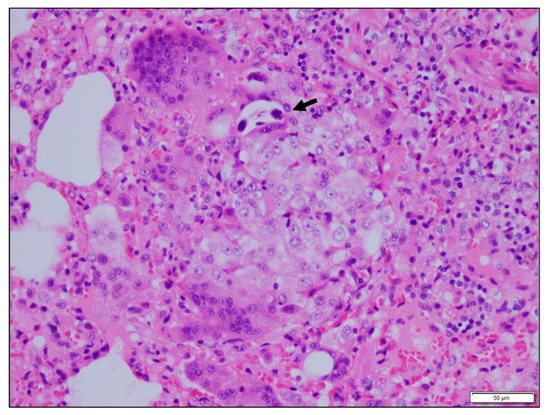

3.3. Histopathological Findings